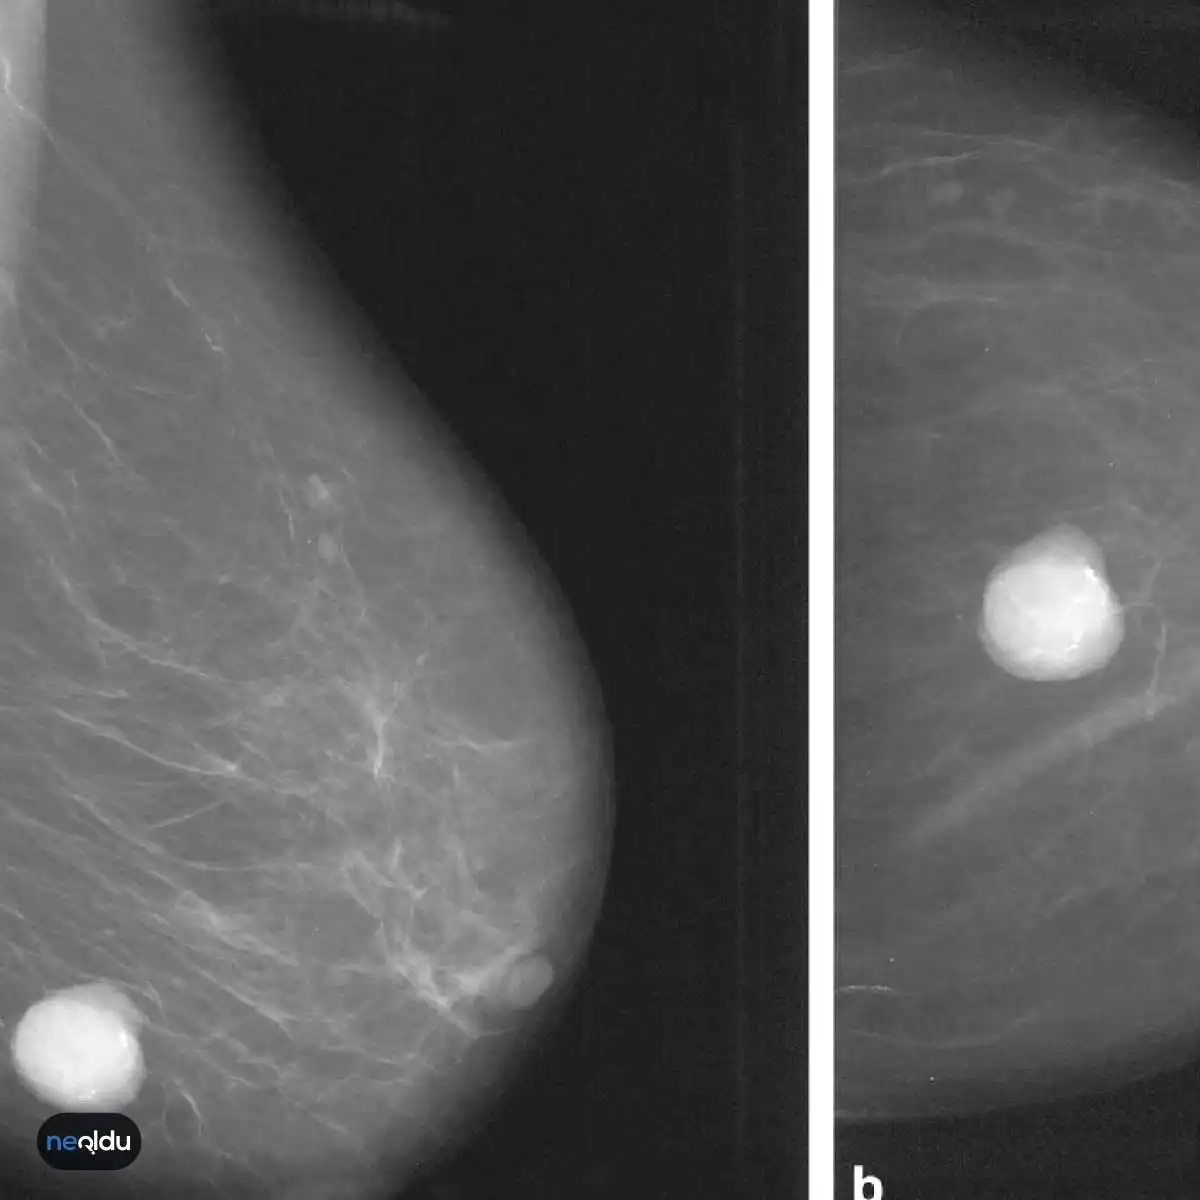

Киста на снимке маммографии

Фиброаденома молочной железы - доброкачественное образование, которое часто встречается у женщин. Оно может быть обнаружено при помощи различных методов диагностики, включая маммографию. Ниже представлены фотографии, помогающие понять, как выглядит данное заболевание.

Маммография и ее роль в диагностике фиброаденомы молочной железы

Маммография - это рентгенологическое исследование молочных желез. Оно позволяет выявить различные изменения в тканях, включая фиброаденому. На маммограммах можно увидеть структурные особенности опухоли и отследить ее динамику во времени.